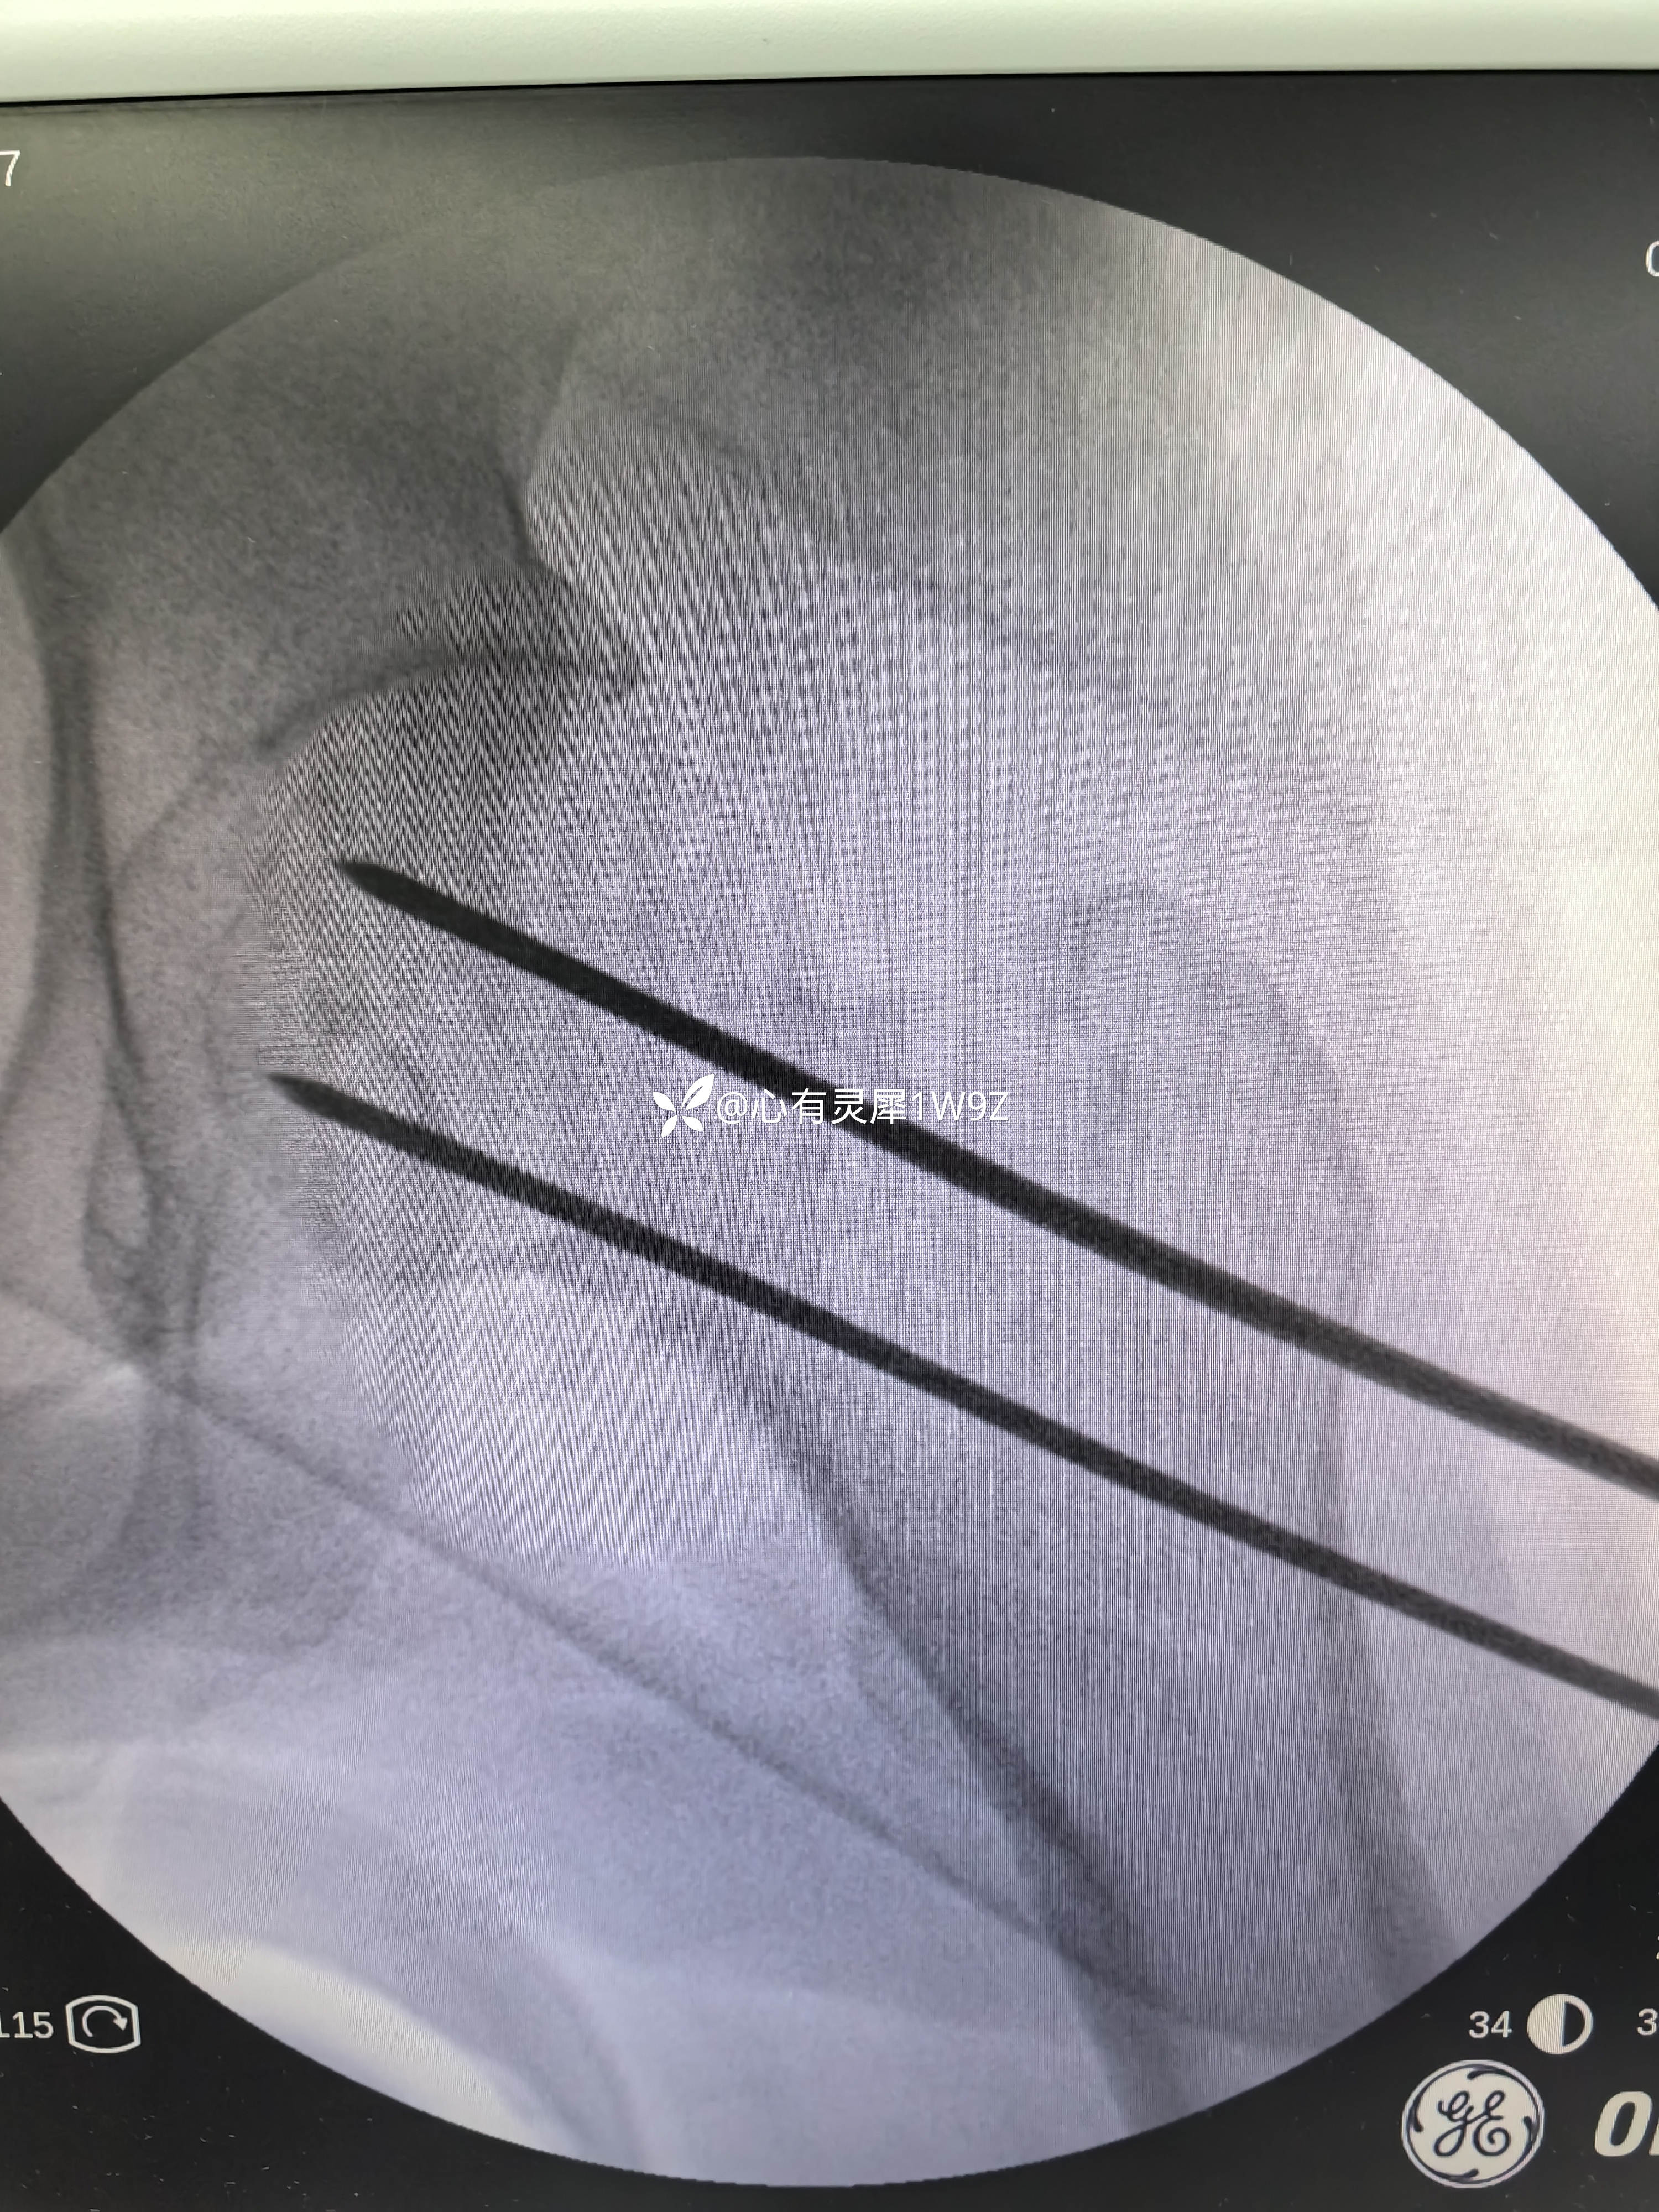

向患者及家属讲解治疗方案。患者和家属选择做内固定。积极准备后在24小时内手术。椎管麻醉,手术顺利,计划首先闭合复位,复位失败就切开复位,三枚加压空心钉固定。

1,关于闭合复位的一些经验,该患者牵引床,先外旋外展牵引解锁后透视正位,根据情况再调整牵引内旋透视复位侧位。最后再内旋内收定位画线。

2,关于贴壁,平行,长度,角度。自己感觉这次平行和长度都比较满意,贴壁还可以,角度不是很完美,感觉可以接受,就没有再调整。